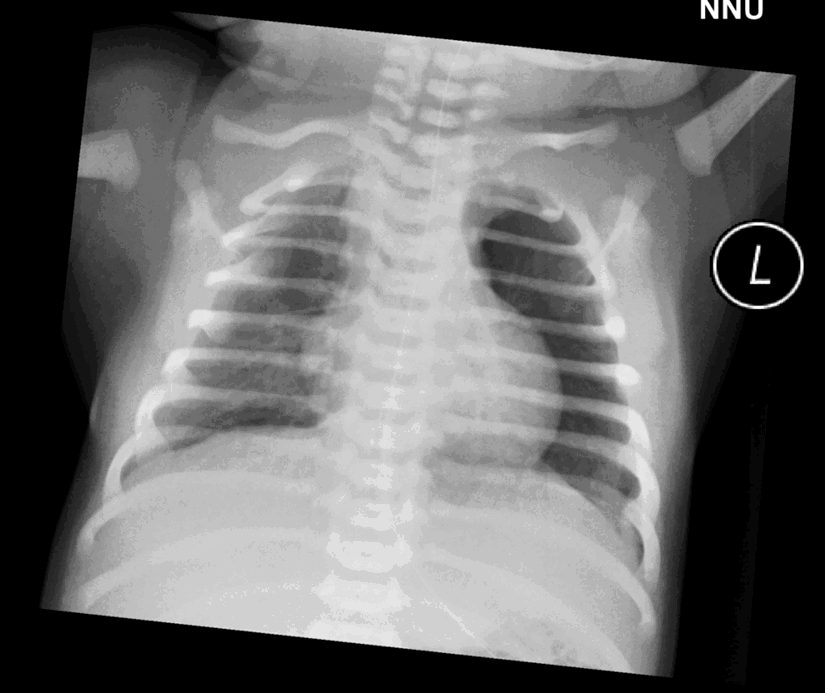

New-born male. Referral from NNU. History: traumatic birth due to shoulder dystocia, query clavicular fracture.

New-born male. Referral from NNU. History: traumatic birth due to shoulder dystocia, query clavicular fracture

Findings:

Appropriately sited NGT

Left pneumothorax

No evidence of tension

No humeral head ossification so likely premature neonate

No fracture or dislocation

Management:

Telephone NNU to alert clinical team about left PTX

| Sample answer | Answer type | Explanation of scoring allocation |

|

-Nasogastric tube passes into stomach, tip not visualised. Urgently phone NNU to ensure findings are known. |

High scoring answer |

This answer would score highly because the observations are correct, the report is well-structured, and the report has been appropriately escalated |

Patient rotated to the left. Notify NICU team. |

Mid scoring answer |

This answer would not score so highly because the candidate is not confident about the left pneumothorax and has over-diagnosed a right clavicular fracture. |

NGT in situ appears satisfactory. no clavicle fracture or dislocation seen. imaged lungs appear normal. No further management |

Low scoring answer |

This answer has scored low marks because the candidate has missed an important finding (left pneumothorax). |